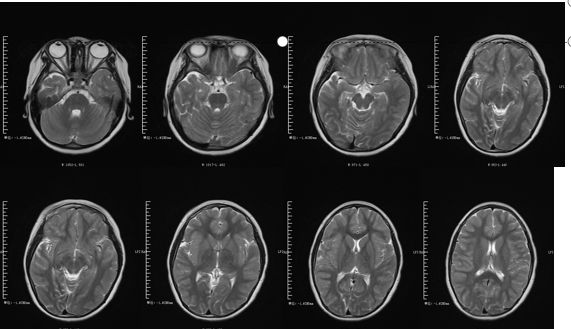

病例10

59岁,男性,急性高热伴视物模糊就诊。查体:左眼视力下降,部分左上睑下垂,左侧轻偏瘫。病情进行性加重,逐渐出现嗜睡、呼吸衰竭、进行性延髓麻痹和自主神经功能障碍(多汗、流涎、心动过速、高血压)。48h后出现面部及四肢无力、反射减弱,转入重症监护室。

4周时MRI:

答案:脑干脑炎与戊型肝炎并发急性多发性神经病。

脑脊液检查:WBC:20*106/L,蛋白1.6g/L,病毒和细菌均阴性。莱姆病、血液传播病毒、梅毒、自身抗体阴性。神经传导提示明显的周围神经受累,急性运动和感觉轴突神经病变。接受了脑干脑炎和格林巴利综合征的感染性和炎症性治疗。完善脑脊液戊肝病毒(HEV)RNA阳性。经过治疗后好转出院。脑干脑炎的病因大致分为:①感染性:李斯特菌、肠道病毒或单纯疱疹病毒感染等;②自身免疫性:多发性硬化、白塞病;③肿瘤和(或)副肿瘤性:与抗Yo抗体和抗Tr抗体相关的副肿瘤综合征。其他罕见的病因包括:JC 病毒感染、CLIPPERS 综合征、淋巴瘤、亚急性硬化性全脑炎等。